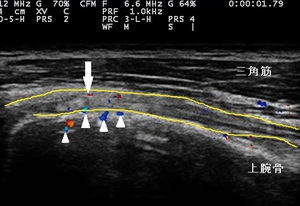

右上腕二頭筋長頭腱 超音波長軸像 左同部 正常(健)側

川越市50代男性、会社員。 右肩、腕の痛み、上腕二頭筋損傷。

1週間経過後も痛みが引かず、腕も挙がらない為、当接骨院を受診されました。超音波観察において右上腕二頭筋

長頭腱(左右上画像の黄色線)に部分的な断裂が認められました(左上画像の矢印)。また、部分断裂部周辺で

炎症反応の血流増生も認められました(左上画像の矢頭)。

上腕二頭筋損傷とは、上腕骨頭部の結節間溝(上腕二頭筋長頭腱が通る溝)で、長頭腱やそれを押さえる

横靭帯が、重い荷物を持ったり転倒して手を突いたりすると圧迫や牽引されてしまい、腱が損傷してしまいます。

来院1週間は右腕を拳上しようとすると痛みが強く拳上不能であった為、痛みや炎症の緩和、長頭腱の損傷部の

修復を促す理学療法を開始しました。また、日常生活では患部にテーピングを貼付し安静保持としました。

2週目には、右腕の拳上時に痛みがありますが、数回拳上動作を繰り返すと痛みが出ないようになりました。

3週目には、違和感はあるものの拳上時の痛みは消失した為、施術終了と致しました。